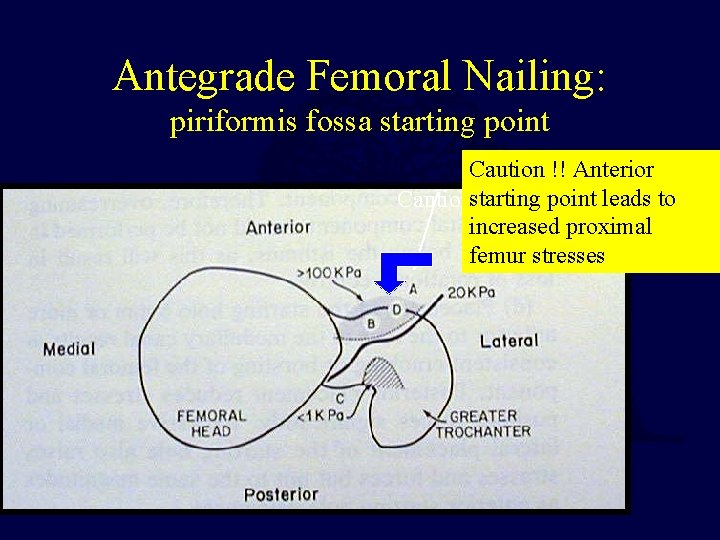

Antegrade Femoral Nailing: piriformis fossa starting point Caution !! Anterior point leads to Cautionstarting !! anterior increased proximal femur stresses

Antegrade Femoral Nailing starting point Posterior loss of proximal fixation Piriformis fossa- proper starting point Anterior - generates huge forces, can lead to bursting of proximal femur